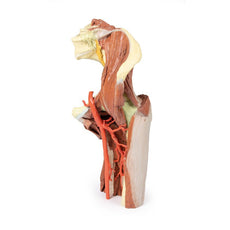

3D Printed Female right pelvis superficial and deep structures

The specimen has been sectioned transversely through the L4 vertebra, displaying a cross section of the colon, the epaxial musculature (psoas and quadratus lumborum muscles), and the abdominal wall musculature. The common iliac artery has been preserved from the level of the L4 vertebra, and its bifurcation into the external and internal iliac arteries can be observed at the level of the sacral promontory. Deep to the arteries the common iliac vein and the origin of the inferior vena cava are visible.

The external iliac artery and vein passes anteroinferiorly along the pelvic brim, giving rise to the inferior epigastric and deep circumflex arteries and veins before passing deep to the inguinal ligament. The psoas major muscle lies lateral to the external iliac artery, with the femoral nerve evident on its lateral margin close to the inguinal ligament. The lateral cutaneous nerve of the thigh travels laterally on the superficial surface of the iliacus muscle to exit the ‘false’ pelvis close to the anterior superior iliac spine.

In the gluteal region (note the femur has been removed to expose the acetabulum) the sciatic nerve can be seen emerging from the greater sciatic foramen (GSF) alongside the inferior gluteal vessels below the remains of the piriformis fibres, whereas the superior gluteal vessels and nerve emerges above the piriformis. Below these vessels the pudendal nerves and vessels can be seen exiting the GSF and passing over the sacrospinous ligament to enter the lesser sciatic foramen, thereby entering the perineum along the lateral wall of the ischioanal fossa.

3D Printed Female right pelvis superficial and deep structures

This 3D printed female right pelvis preserves both superficial and deep structures of the true and false pelves, as well as the inguinal ligament, the obturator membrane and canal, and both the greater and lesser sciatic foramina. Somewhat unique is the removal of portions of the peritoneum (a grayish colour) to create ‘windows’ displaying extraperitoneal structures.The specimen has been sectioned transversely through the L4 vertebra, displaying a cross section of the colon, the epaxial musculature (psoas and quadratus lumborum muscles), and the abdominal wall musculature. The common iliac artery has been preserved from the level of the L4 vertebra, and its bifurcation into the external and internal iliac arteries can be observed at the level of the sacral promontory. Deep to the arteries the common iliac vein and the origin of the inferior vena cava are visible.

The external iliac artery and vein passes anteroinferiorly along the pelvic brim, giving rise to the inferior epigastric and deep circumflex arteries and veins before passing deep to the inguinal ligament. The psoas major muscle lies lateral to the external iliac artery, with the femoral nerve evident on its lateral margin close to the inguinal ligament. The lateral cutaneous nerve of the thigh travels laterally on the superficial surface of the iliacus muscle to exit the ‘false’ pelvis close to the anterior superior iliac spine.

In the gluteal region (note the femur has been removed to expose the acetabulum) the sciatic nerve can be seen emerging from the greater sciatic foramen (GSF) alongside the inferior gluteal vessels below the remains of the piriformis fibres, whereas the superior gluteal vessels and nerve emerges above the piriformis. Below these vessels the pudendal nerves and vessels can be seen exiting the GSF and passing over the sacrospinous ligament to enter the lesser sciatic foramen, thereby entering the perineum along the lateral wall of the ischioanal fossa.